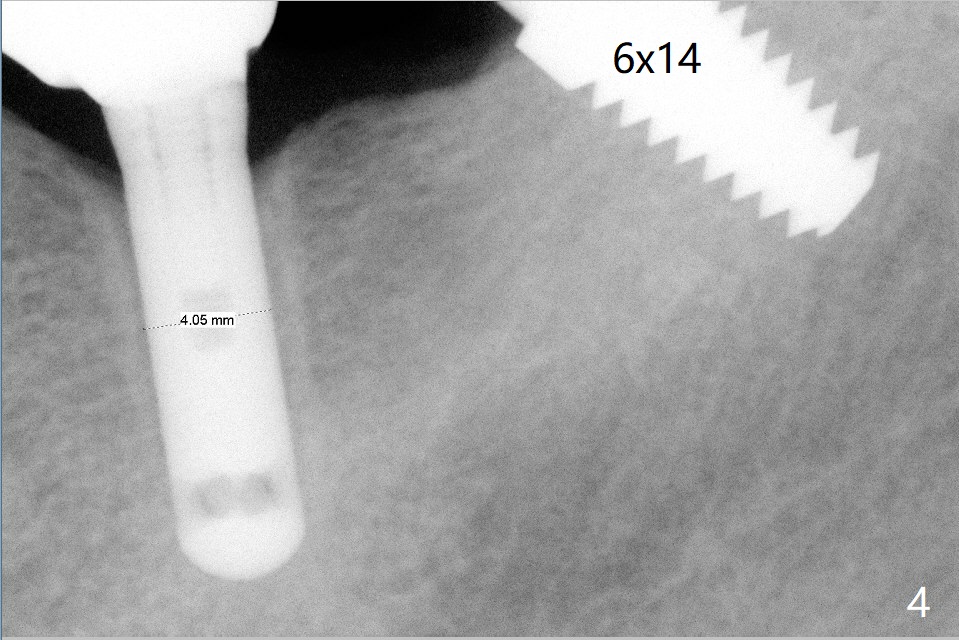

A 69-year-old man needs an implant at #18 (Fig.1,2 CT (sagittal and coronal sections)). In spite of use of surgical stent, the trajectory is not ideal (Fig.3-5). The following day the implant is removed with bone graft (Fig.6). In the 2nd placement, the trajectory is adjusted in each step (Fig.7-9 arrows) with long term stability (Fig.10,11).